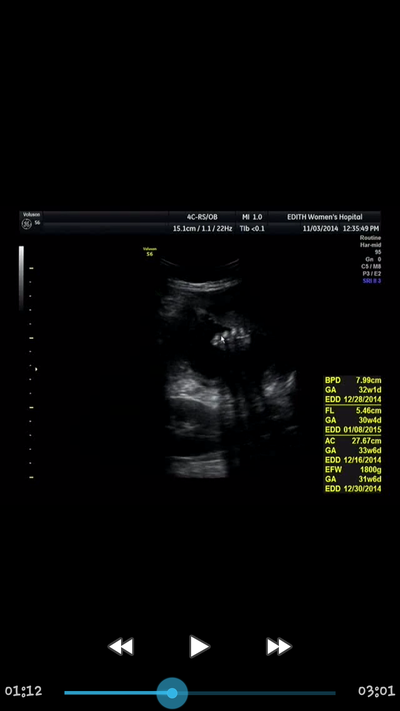

임신 31주 4일/태아콩팥크기/태아부정맥